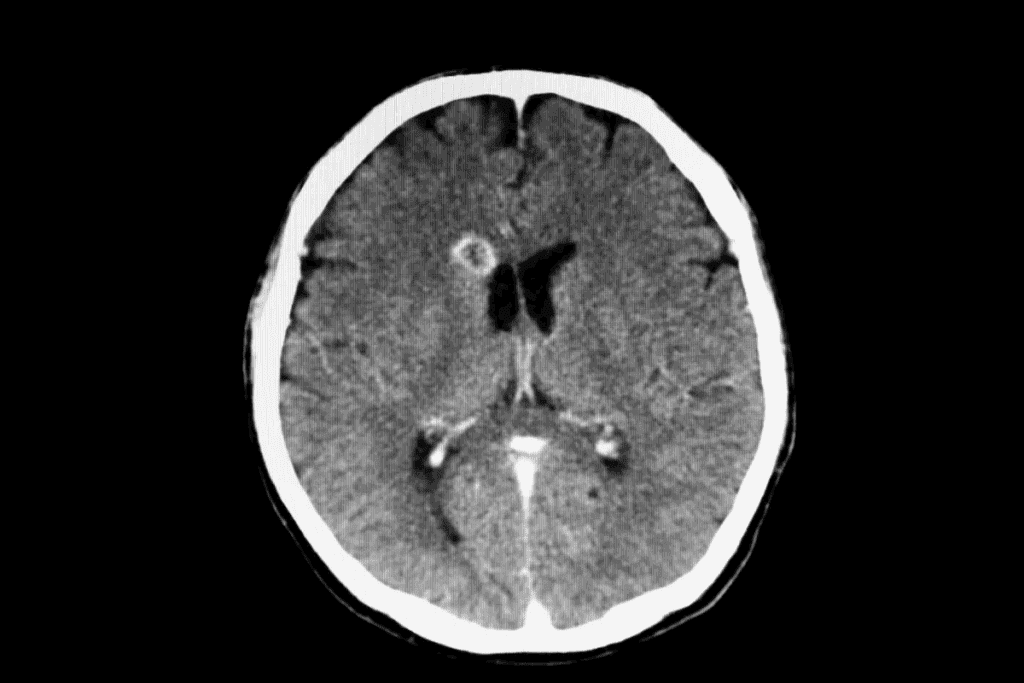

Interpreting CT Scan Results: What Do Brain Tumors Look Like?

Reading CT scans correctly is key to spotting brain tumors and what they mean. CT scans show detailed brain images. This helps doctors find any oddities.

Common Appearances of Different Tumor Types

Brain tumors look different on CT scans. This depends on their size, type, and where they are. Some tumors are clear and have sharp edges. Others are harder to see and spread out.

Meningiomas look like dense, round shapes near the brain’s surface. They stick to the dura mater. On the other hand, glioblastomas are irregular and have dead spots and swelling around them.

It’s important to know the terms in these reports. “Hypodense,” “hyperdense,” and “isodense” describe how the tumor looks compared to the brain. The report might also mention if the tumor shows up well with contrast. This can tell us about the tumor’s blood supply and if it might be cancerous.